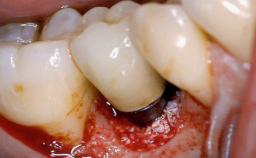

Treatment of Peri-Implantitis at a Zirconia Implant

Due to their promising clinical performance, zirconia implants have recently become popular alternatives to titanium implants, particularly for areas with high esthetic demands (Holländer and coworkers 2016; Roehling and coworkers 2016; Lorenz and coworkers 2019). However, regardless of the reported high survival and success rates, zirconia implants were affected by peri-implant diseases over the short observation period, suggesting the importance of treating peri-implant diseases at zirconia implants (Becker and coworkers 2017). In their case, Frank Schwarz and Ausra Ramanauskaite present 3-year results following mechanical debridement alongside Er:YAG laser monotherapy.